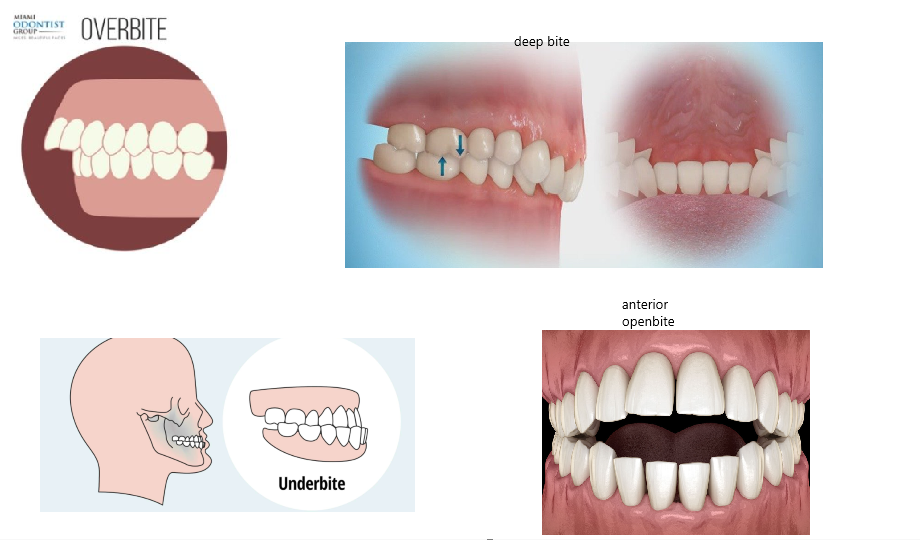

4. you need to have bite issues, extreme overbite(7 mm +), underbite, deep bite, or anterior open bite(get your condyles checked).(you can create via decomp)

4. you need to have bite issues, extreme overbite(7 mm +), underbite, deep bite, or anterior open bite(get your condyles checked).(you can create via decomp)